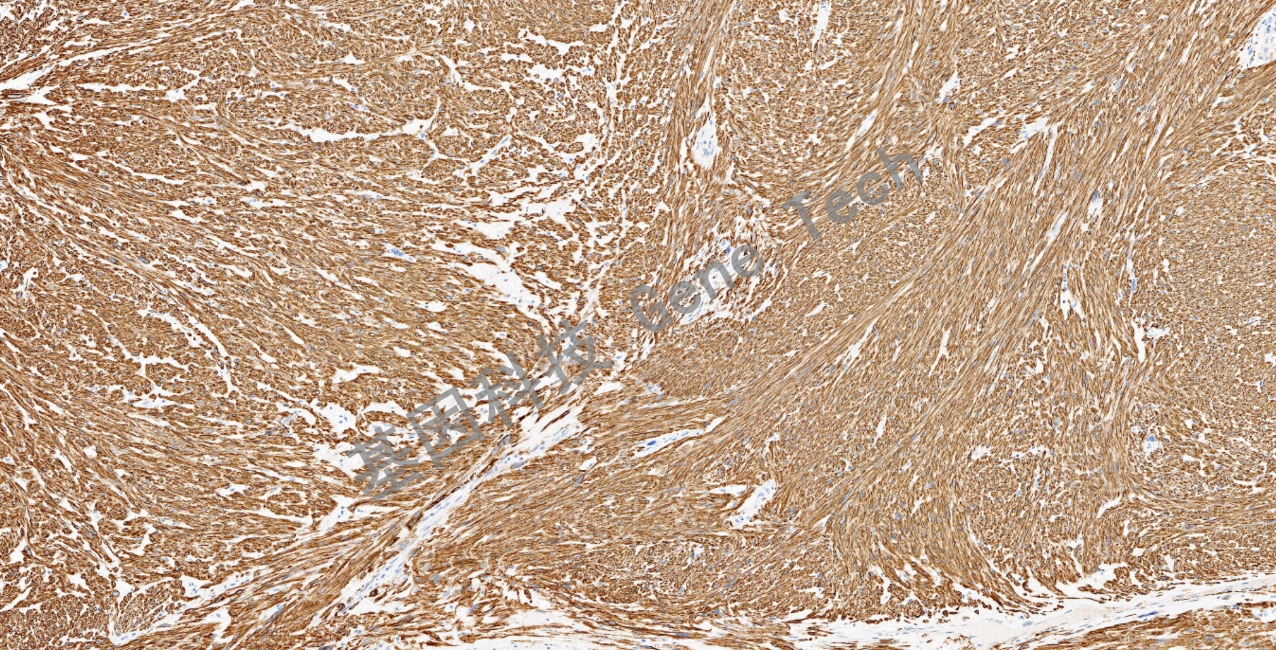

平滑肌肉瘤石蜡切片,用 Desmin(GT2252)染色,细胞浆阳性,DAB 显色。